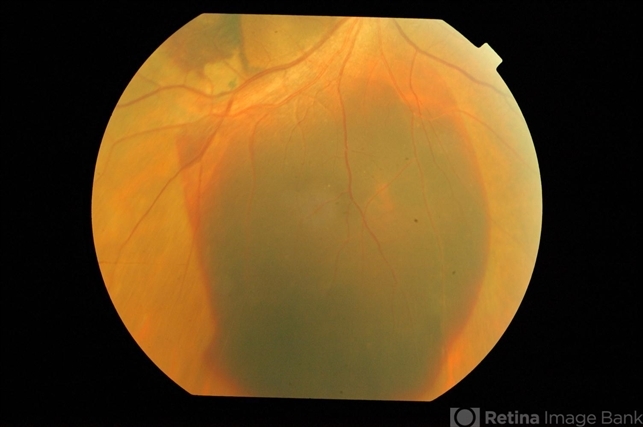

- Submacular heme in wet AMD

- submacular hemorrhage

- Inferiorly displaced subretinal heme 24 hours after gas injection and prone positioning for wet AMD with submacular hemorrhage.